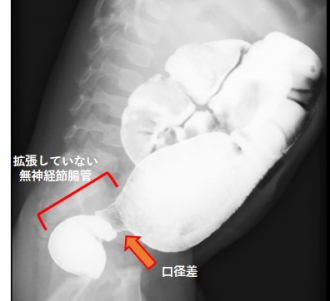

注腸検査は肛門から管を挿入し造影剤を口側に向かって流していきます。本症の場合は無神経節腸管が細く、その口側の腸が拡張しているのが特徴です。

この所見がみられた場合、確定診断のため直腸粘膜生検を入院して行います。採取した組織内に神経節細胞がみられなければ診断が確定します。